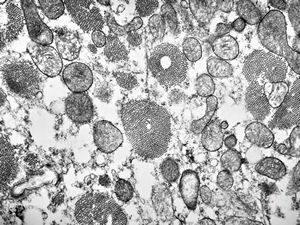

M, 7w. | mitochondrial cardiomyopathy (N - nucleus, M - megamitochondria,R - dilated endoplasmic reticulum)- autopsy sample

M, 7w. | mitochondrial cardiomyopathy … (N … nucleus, F … myofilaments,L … lipid droplets surrounded by megamito